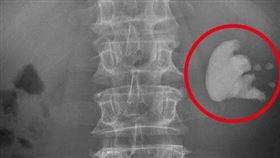

健檢發現輸尿管結石 驚見這女人有三顆腎

臺中市62歲張女士,今年1月到醫院健檢,發現左側輸尿...

結石纏他30年 「鹿角結石」險奪命

尿路結石的難纏和發作時的疼痛,只有患者自己最清楚。台...